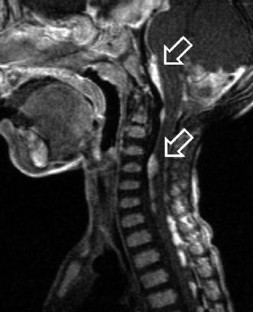

Fig. 1.